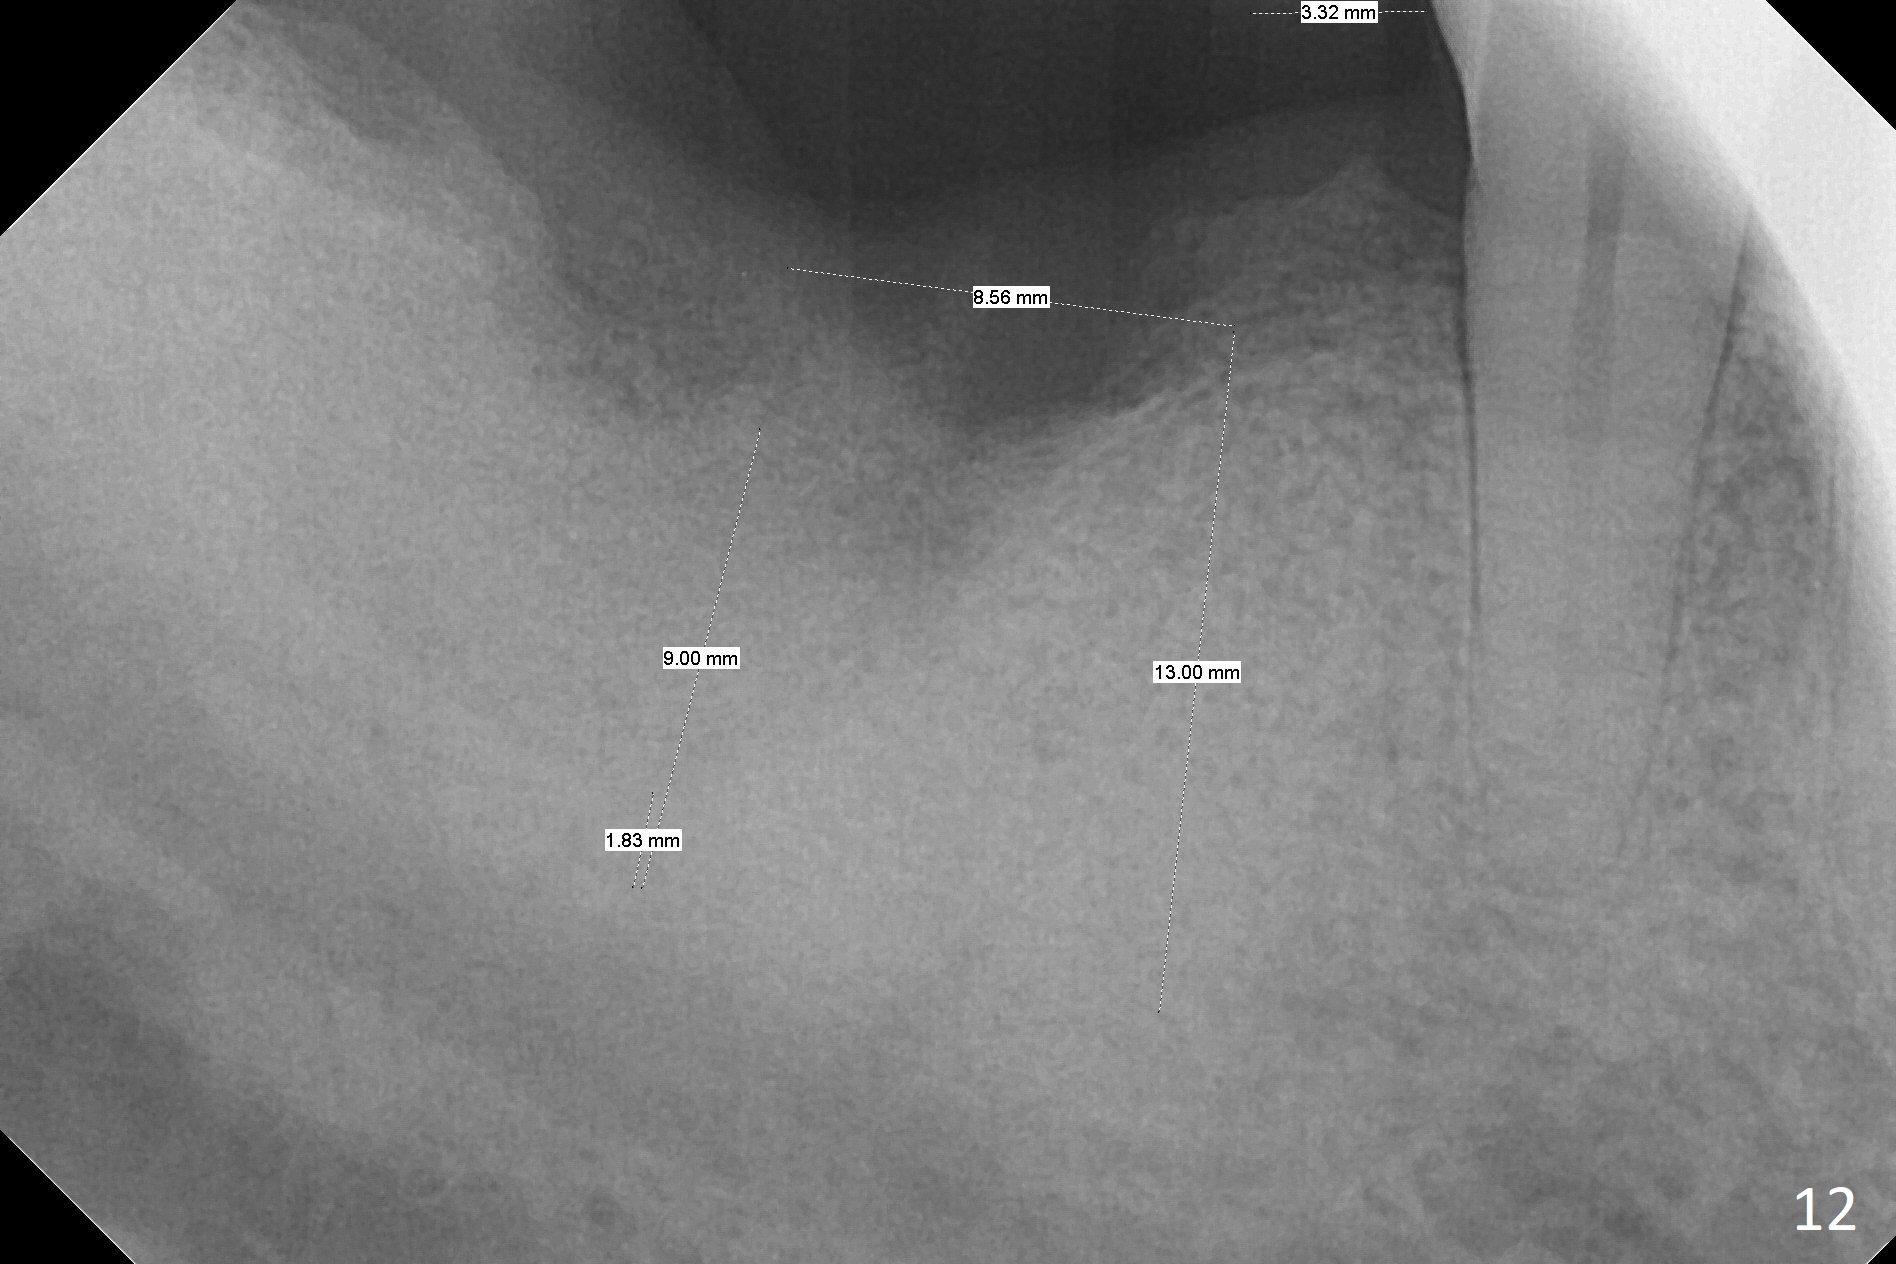

The socket heals 3 months postop (Fig.8,11). There is vertical loss of the ridge at #31 (Fig.9,10). The implant placed at #31 will be shorter than that at #30 (Fig.12). The patient will return for implant placement 4 months postop.